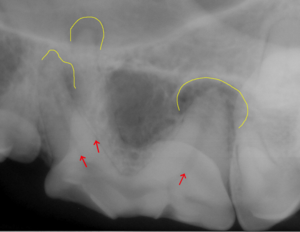

● 歯の破折 3 : 根先膿瘍の放置による目の下の開放創

この3枚の写真に示されるように①は根先部に膿瘍が認められます。②は膿瘍部分に黄色く色づけをしてみました。③は逆サイドの正常な写真になります。![]()